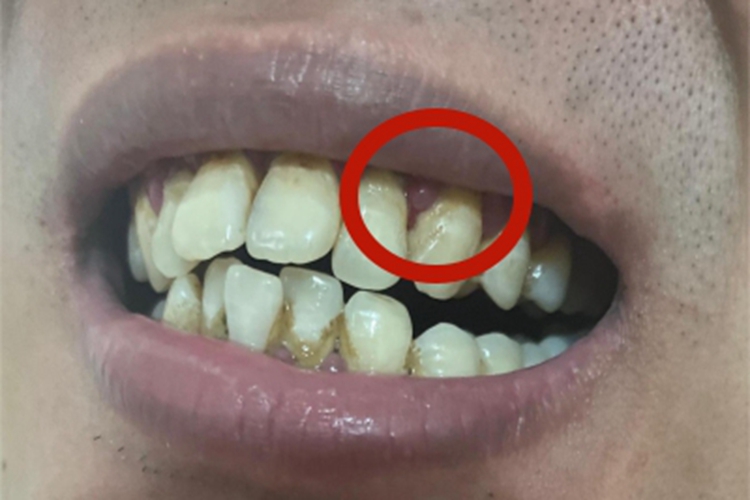

急性浆液性根尖周炎可表现为牙间隙处牙龈肿胀,明显突出黏膜表面,像突出个小包一样,表面可有血浆渗出,同时伴随牙根发痒、咬合时疼痛等症状。